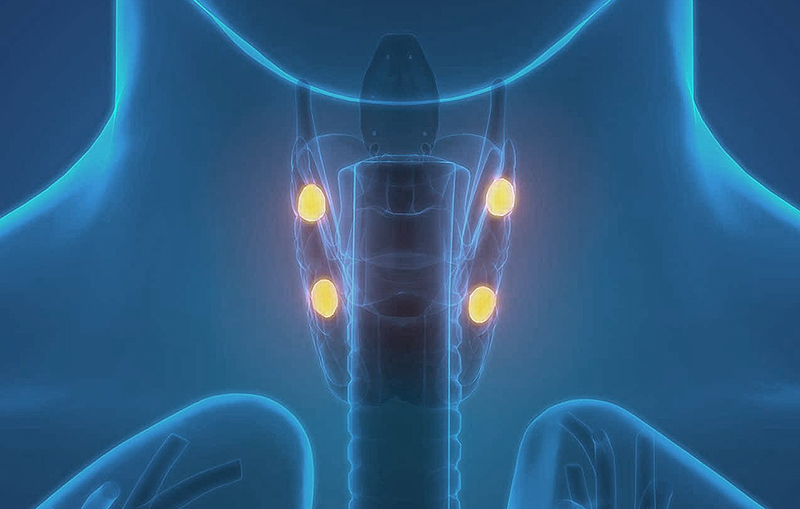

Иллюстрации и схемы по остеопорозу и паращитовидной железе